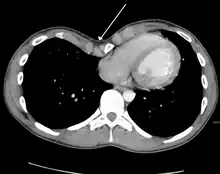

Many scales have been developed to determine the degree of deformity in the chest wall. Most of these are variants on the distance between the sternum and the spine. One such index is the Backer ratio which grades severity of deformity based on the ratio between the diameter of the vertebral body nearest to xiphosternal junction and the distance between the xiphosternal junction and the nearest vertebral body.[17] More recently the Haller index has been used based on CT scan measurements. An index over 3.25 is often defined as severe.[18] The Haller index is the ratio between the horizontal distance of the inside of the ribcage and the shortest distance between the vertebrae and sternum.[19]

Chest x-rays are also useful in the diagnosis. The chest x-ray in pectus excavatum can show an opacity in the right lung area that can be mistaken for an infiltrate (such as that seen with pneumonia).[20] Some studies also suggest that the Haller index can be calculated based on chest x-ray as opposed to CT scanning in individuals who have no limitation in their function.[21]

Pectus excavatum requires no corrective procedures in mild cases.[22] Treatment of severe cases can involve either invasive or non-invasive techniques or a combination of both. Before an operation proceeds several tests are usually performed. These include, but are not limited to, a CT scan, pulmonary function tests, and cardiology exams (such as auscultation and ECGs).[23] After a CT scan is taken, the Haller index is measured. The patient's Haller is calculated by obtaining the ratio of the transverse diameter (the horizontal distance of the inside of the ribcage) and the anteroposterior diameter (the shortest distance between the vertebrae and sternum).[24] A Haller Index of greater than 3.25 is generally considered severe, while normal chest has an index of 2.5.[19][25][26] The cardiopulmonary tests are used to determine the lung capacity and to check for heart murmurs.[27]